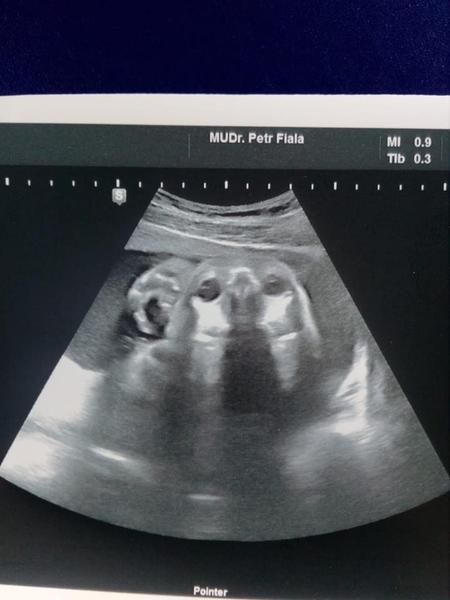

@val333 jo fakt nonstop...v noci když se probudím tak je klid...takže doufám v to, že v noci spí a přes den je vzhůru :D dnes jsem byla v poradně a neuvěřitelně se tam hýbalo....jakoby ukazovalo "Hele mami co už všechno umím"...viděla jsem pohyb očiček, pusy a pak mě čelíčkovalo...takže už vím čím jsou způsobené ty největší rány pod hrudníkem...prostě dělá berany berany duc... :D

Jinak děvčata...dnes mě můj muž pobavil tak, až jsem výbuchem smíchu vyprskla polívku...přišel domů z práce a tak mu ukazuju krásné selfie mimča, které se dnes vyvedlo...a on mi říká: " Teda...ty moc dobře víš, jak jsem si vždycky přál pejska...ale že se to stane takhle..." :D :D :D :D a pak koukám a fakt že jo...máme malého kokříka...ty uši, čumáček, očička a jak se směje :D :D :D :D no ještě teď se směju já...